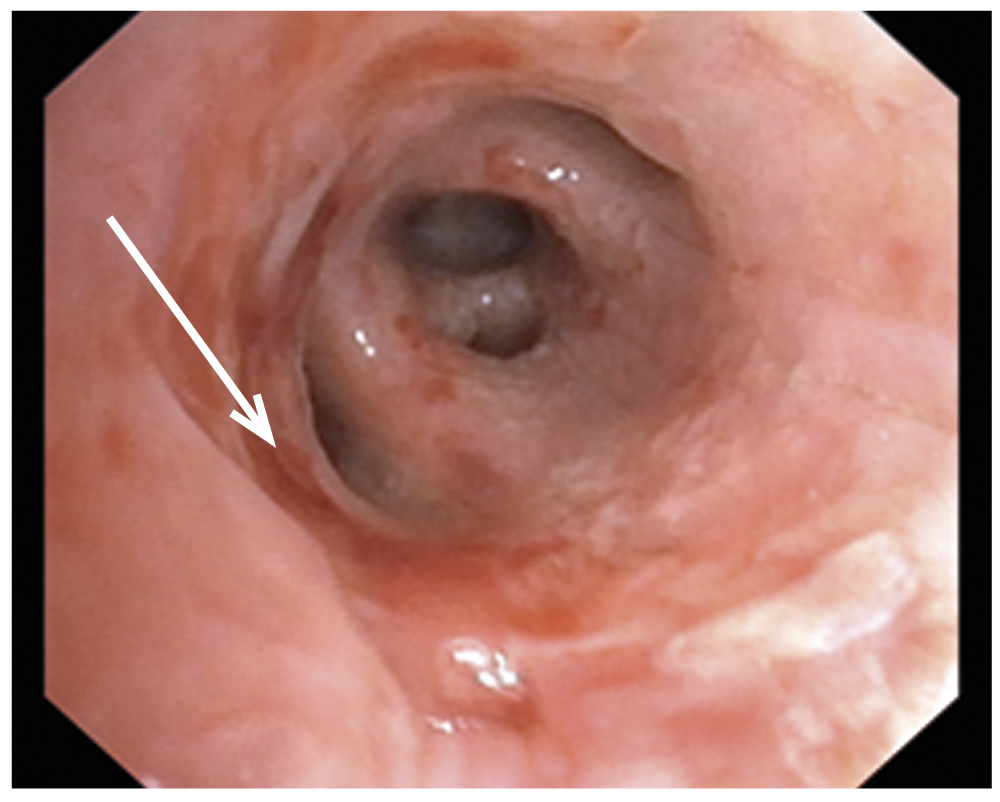

На фоне проводимой терапии, включая ИВЛ, к 5-м сут посттравматического периода отмечена положительная динамика в виде устойчивой стабилизации гемодинамики без вазопрессорной поддержки. Однако продувание воздуха по дренажам сохранялось. На фоне использования интермиттирующего (пассивного и активного) режима аспирации не удавалось достичь устойчивого полного расправления паренхимы правого лёгкого. Газовый состав крови сохранялся субкомпенсированным, сатурация 90–95% с периодами снижения до 80–84%. Учитывая стабилизацию гемодинамических показателей консилиумом реаниматологов, хирургов и врачей-эндоскопистов было принято решение выполнить диагностическую ларинготрахеобронхоскопию (ЛТБС) для определения возможности установки бронхоблокатора с целью окклюзии бронхопульмонального свища. ЛТБС проводили в условиях операционной под общей анестезией, через воздуховод I-GEL бронхоскопом 4,9 мм с инструментальным каналом 2,0 мм. Манипуляцию проводили под рентгенологическим контролем (электронно-оптический преобразователь — С-дуга). Для предотвращения бронхоспазма голосовые складки и карину дополнительно орошали 2% раствором лидокаина гидрохлорида моногидрата в возрастной дозировке. В просвете трахеобронхиального дерева, больше справа, выявлено значительное количество вязкой густой слизи с примесью крови. Выполнена санация трахеобронхиального дерева с промыванием антисептическим раствором с последующим детальным осмотром всех видимых бронхов левого и правого лёгкого. По передней стенке промежуточного бронха визуализирован линейный разрыв 9×3 мм с неровными краями (рис. 2).

Рис. 2. Эндоскопическая картина: травматический разрыв 9×3 мм по передней стенке промежуточного бронха.

Fig. 2. Endoscopic picture: traumatic rupture of 9×3 mm along the anterior wall of the intermediate bronchus.